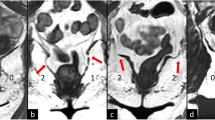

For the gluteus, retroversion increased CSA and circularity (Table 5, Fig. 2, Fig. 3a). This effect was consistent across levels L5/S1, S1/S2, and max FH, where there was up to a 22% increase from standing or flexion to retroversion (Table 5, Fig. 2a–c; Fig. 3a). However, this effect with retroversion varied at S4/S5 where there was no change in CSA, but increased circularity (Table 5; Fig. 2d–f; Fig. 3b).

Example changes in gluteus CSA (yellow) and circularity (Circ, green) with posture (↓ = decrease, ↑ = increase, – = no change). At max FH for both CSA and circularity, there was up to a 15% decrease from supine to standing (a, b) and up to a 22% increase from standing or flexion to retroversion (b to c). At S4/S5, from supine to standing though CSA decreased by 16%, there was no change in circularity (d, e). Additionally, from standing or flexion to retroversion, though there was no change in CSA, circularity increased up to 24% (e, f).